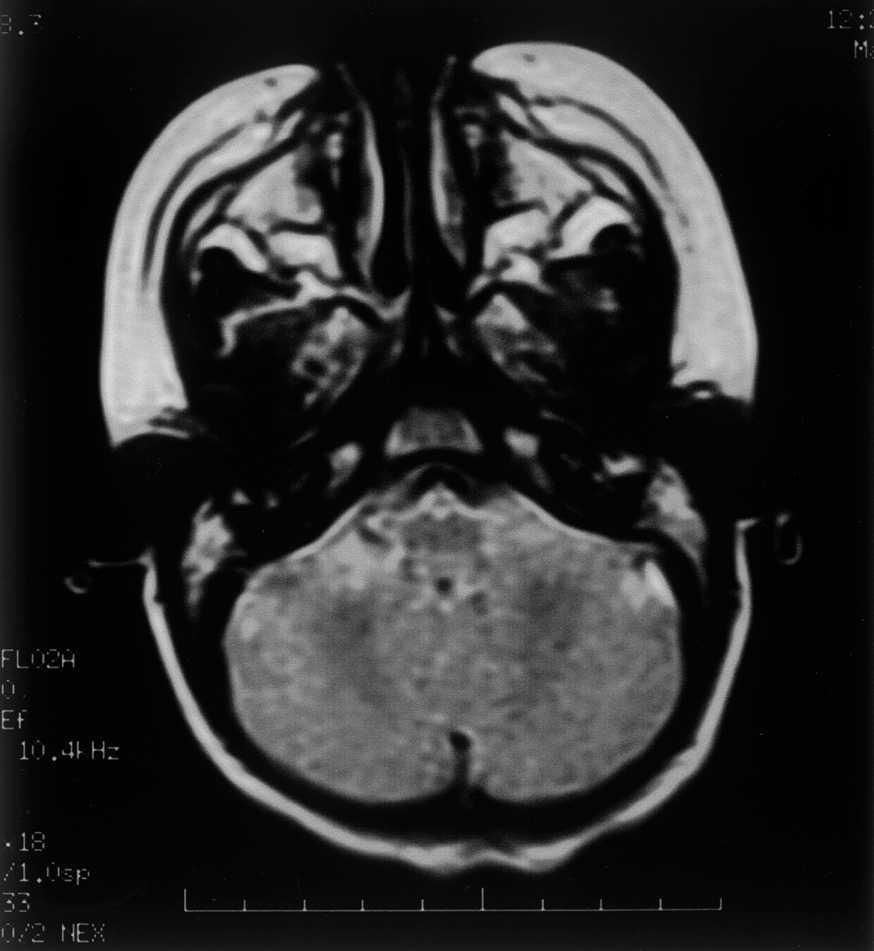

Las exploraciones complementarias realizadas fueron normales: hemograma, bioquímica sérica elemental, creatinfosfocinasa, ácido láctico, piruvato, aminoácidos en suero, ácidos orgánicos en orina, ácidos grasos libres en plasma, carnitina sérica total, carnitina libre, acilcarnitina, cociente acil/libre, equilibrio acidobásico, amonio, hormonas tiroideas, cariotipo, citoquímica de líquido cefalorraquídeo, electromiograma y velocidad de conducción motora de nervio peroneo, biopsia de músculo con estudio estructural, histoquímico y de cuantificación de enzimas de la cadena respiratoria mitocondrial, estudio del ADN mitocondrial de músculo en búsqueda de las mutaciones T8993G, T8993C y A9176C, deleciones únicas o múltiples y depleción por Southern blot, test de edrofonio, estudio de potenciales evocados auditivos del tronco cerebral y una tomografía computarizada (TC) craneal (fig. 1). Se realizaron tres estudios de resonancia magnética (RM) craneal a los 7, 9 y 15 meses de vida que mostraron alteración en la intensidad de la señal en tegmento mesencefálico, pontino y bulbar, más marcado en regiones dorsales (figs. 2 y 3).

Figura 1.TC craneal a nivel del IV ventrículo: ausencia de hallazgos patológicos.